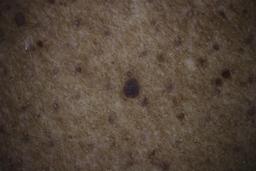

ISIC_6598546

Clinical

| Field | Value |

|---|---|

| age_approx | 60 |

| anatom_site_1 | Trunk |

| anatom_site_2 | Posterior trunk |

| concomitant_biopsy | False |

| dermoscopic_type | contact polarized |

| diagnosis_1 | Benign |

| diagnosis_confirm_type | single contributor clinical assessment |

| fitzpatrick_skin_type | VI |

| image_manipulation | instrument only |

| image_type | dermoscopic |

| lesion_id | IL_6711989 |

| patient_id | IP_8590441 |

| sex | male |